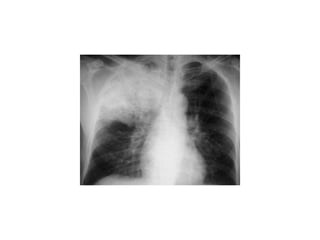

Loss of Sharp Costophrenic Angles

Finally, Check the Lung Fields

• Infiltrates

• Increased interstitial markings

• Masses

• Absence of normal margins

• Air bronchograms

• Increased vascularity